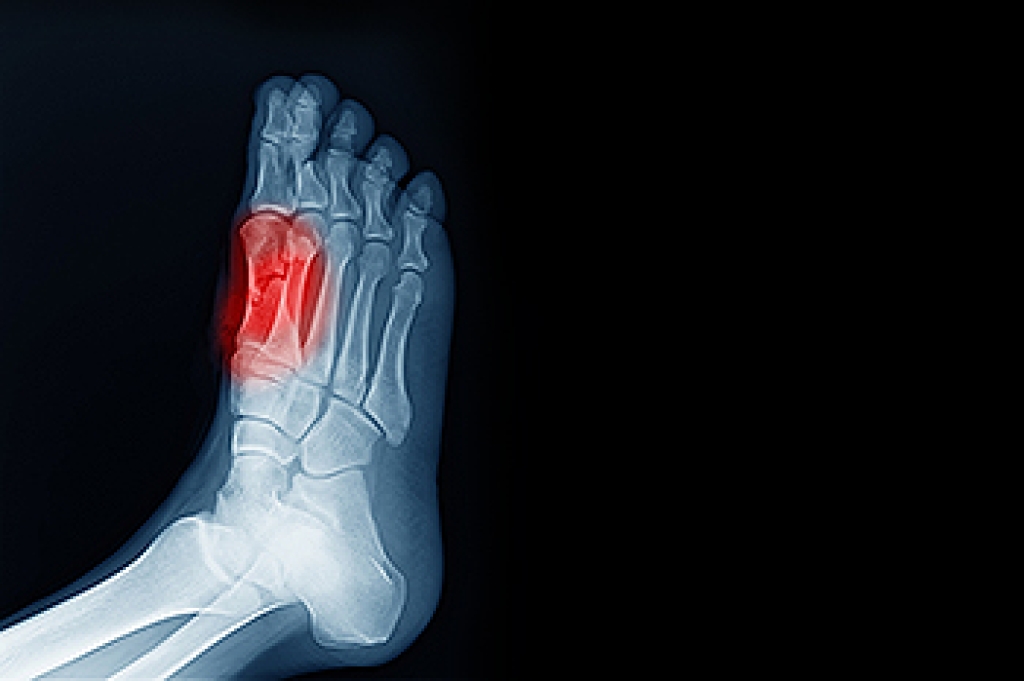

What Kinds of Foot Problems Can Develop from Wearing High Heels?

- Bunions

- Morton’s Neuroma

- Plantar Fasciitis